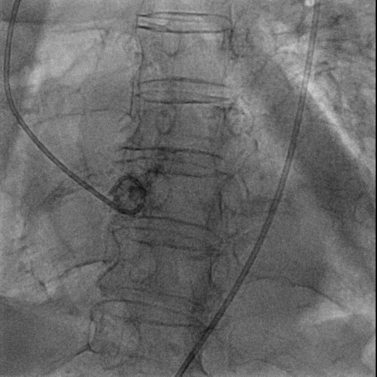

经右股静脉置入7F JR指引导管至下腔静脉,经右股动脉置入6F猪尾导管至腹主动脉,于下腔静脉及腹主动脉同时造影精确定位目标穿刺点。

穿刺系统与圈套器配合完成穿刺并建立下腔静脉至腹主动脉的通路

将0.014英寸导丝交换为超硬导丝后,置入22F大鞘达腹主动脉内。

经右侧股静脉沿超硬导丝置入22F大鞘达腹主动脉内